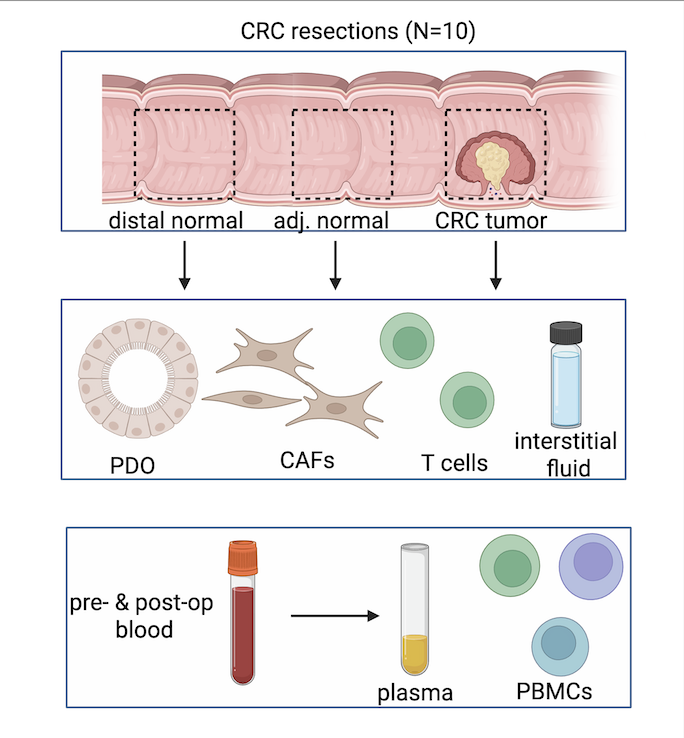

- Administrative Supplement to Cancer Center Support Grant (CCSG); grant supplement for organoid work through the P30 Vanderbilt Cancer Center Support Grant, writer and editor for all components including Project Summary Abstract, Project Narrative, Specific Aims and Research Plan, took leadership role in managing team during hospitalization of managing PI (Total amount: $750,000 for 1 year)

Glass SE, Bechard ME, Cao Z, Aramandla R, Zhao P, Ellis ST, Green EH, Fisher EG, Smith RT, Sievers CK, Irudayam MJ, Revetta F, Washington MK, Ayers GD, Heiser CN, Simmons AJ, Xu Y, Wang Y, Windon A, Shrubsole MJ, Markham NO, Liu Q, Lau KS, Coffey RJ. Dipeptidase-1-knockout mice develop invasive tumors with features of microsatellite-unstable colorectal cancer. JCI Insight. 2025 Apr 3;10(9):e186938. doi: 10.1172/jci.insight.186938. PMID: 40178918; PMCID: PMC12128987.

Heiser CN, Simmons AJ, Revetta F, McKinley ET, Ramirez-Solano MA, Wang J, Kaur H, Shao J, Ayers GD, Wang Y, Glass SE, Tasneem N, Chen Z, Qin Y, Kim W, Rolong A, Chen B, Vega PN, Drewes JL, Markham NO, Saleh N, Nikolos F, Vandekar S, Jones AL, Washington MK, Roland JT, Chan KS, Schürpf T, Sears CL, Liu Q, Shrubsole MJ, Coffey RJ, Lau KS. Molecular cartography uncovers evolutionary and microenvironmental dynamics in sporadic colorectal tumors. Cell. 2023 Dec 7;186(25):5620-5637.e16. doi: 10.1016/j.cell.2023.11.006. PMID: 38065082; PMCID: PMC10756562.